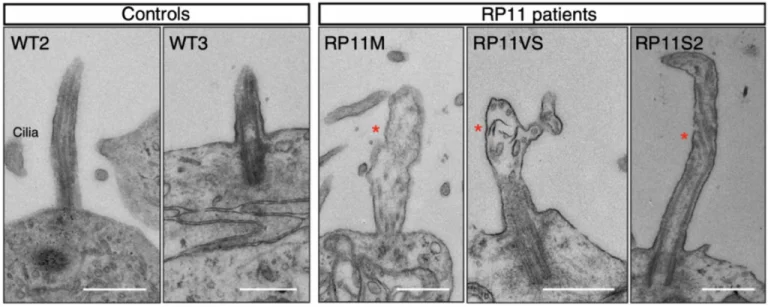

Transmission electron microscopy images showing shorter cilia in patient-derived photoreceptors, with abnormal bulbous morphology (red star). Scale bar (500 nm). Image Credit: Newcells Biotech

After creating retinal organoids from RP Type 11 patients with a mutation in the pre-mRNA processing factor 31 (PRPF31), the mechanism behind the retinal dysfunction in this disease has been clarified.

Large-scale transcriptome analyses that revealed patient-specific and cell type-specific mis-splicing of PRPF31 target genes impacted by PRPF31 mutations made unprecedented molecular characterization of splicing-factor RP clinical phenotypes possible.

This study uncovered several cellular defects, including progressive cellular degeneration, altered cilia morphology in photoreceptors, dysfunctional RPE, and cellular stress, as demonstrated by phenotypic rescue. The study was the first to use patient-derived organoids, or RPEs, to demonstrate the cellular phenotypes linked to RP.

This research and expertise were developed in the lab of Prof. Lako, a co-founder of Newcells Biotech and a professor of stem cell sciences at Newcastle University’s Biosciences Institute, Faculty of Medical Sciences.